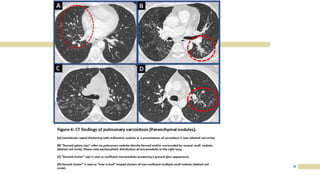

CHEST X RAY

IN

SARCOIDOSIS

17

18